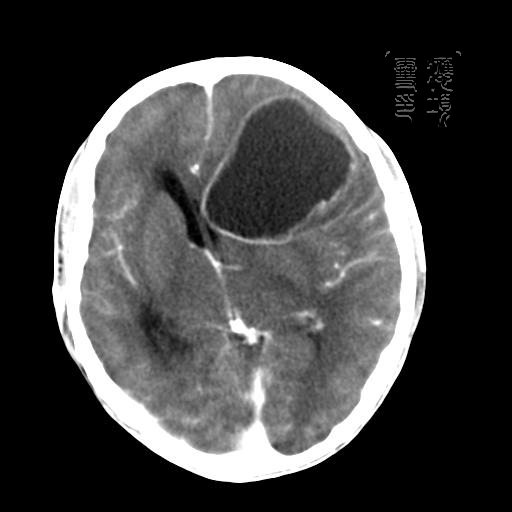

m 52y

二月前癫痫入院, 无既往史,现头痛、呕吐、视力减退、复视行ct平扫及增强检查。

左额叶囊实性占位,以囊性为主,并见明显强化不规则壁结节,占位效应明显,首先考虑是囊性星形细胞瘤.

谢谢楼上的朋友们!

结果已经在最后一幅图片内,感兴趣的,另存此图用记事本打开,往下拉就可看到。